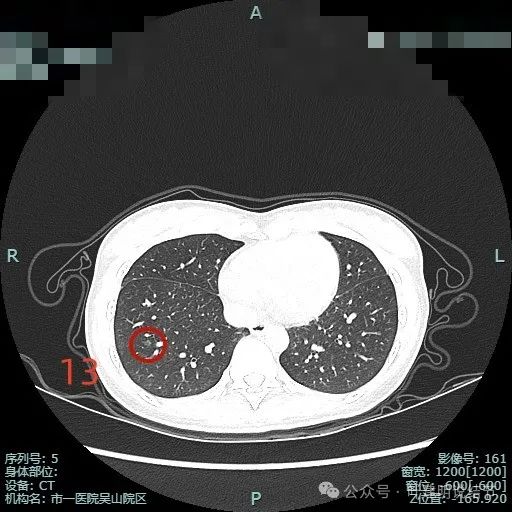

病灶13:右下叶淡磨玻璃结节,整体轮廓较清,考虑肺泡上皮增生或不典型增生可能。